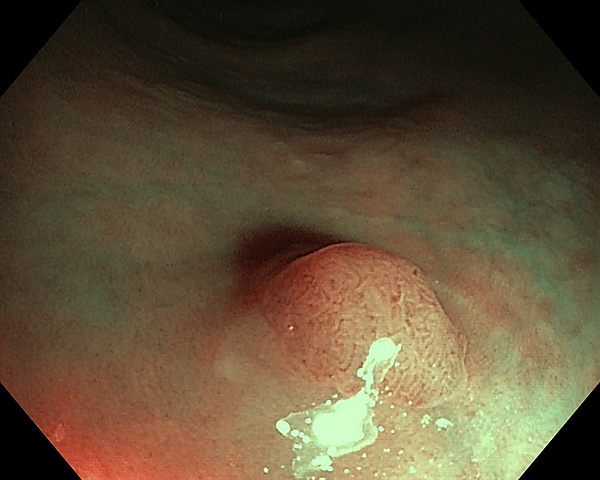

Колоноскопи́я, также фиброколоноскопия или ФКС — медицинский эндоскопический диагностический метод, во время которого врач осматривает и оценивает состояние внутренней поверхности толстой кишки при помощи эндоскопа. Колоноскопия даёт возможность визуально диагностировать такие заболевания, как образование язвы, полипы и др., а также провести биопсию и удалить эти поражения. Колоноскопия позволяет удалять полипы размером от долей миллиметра до 30-40 мм (в зависимости от их строения решение об удалении принимается во время первичного осмотра). Сразу после удаления полипа его можно исследовать в гистологической лаборатории и определить тип его строения. Это поможет спрогнозировать риски развития онкологических заболеваний у пациента в дальнейшем.

Удаление полипов при колоноскопии - важная процедура, позволяющая исключить вероятность развития злокачественного перерождения полипа.